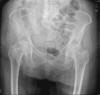

APR Fractura de pelvis